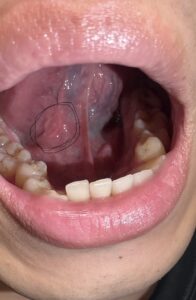

口内炎 お昼ご飯を食べたあと(13時半頃)に舌で口の中をぐるぐるしていたら、ポツっとした デキモノができているのに気づいて「ただの口内炎だろう」と思って鏡で見てみる と、赤黒い(ほぼ黒色の)血マメみたいなモノができていました。

黒丸印は口内炎でしょうか?それとも舌癌?でしょうか。 2026.02.18 毎日、痛くて、食事すらまともにとれません。 A.こんにちは、安原歯科医院の安原豊人です。 お写真拝見いたしました。 おそらく口内炎です。ご安心ください。 口内炎の塗り薬を処方してもらってこまめに塗布することをお勧めいたします。 ただしその後1週間たっても改善が認められなければ、 お近くの口腔外科を受診されることをお勧めいたします。 口腔外科専門医 安原豊人 歯や、あご、お口の中のことで、疑問がございましたら、何でもお気軽にご相談ください。 Tweet Share Hatena Pocket RSS feedly Pin it この記事のタイトルとURLをコピーする 数日前、みかんを食べている時に舌が痛いので鏡を見ると舌の側面が写真のように変化があるのに気づきました。 前の記事 舌の奥の方に赤いブツブツ(画像より広範囲です)と白いできものがあります。 次の記事